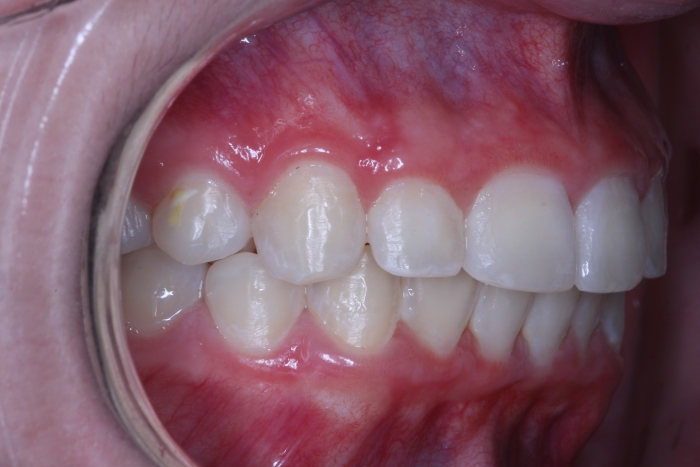

Lateral final - 2019